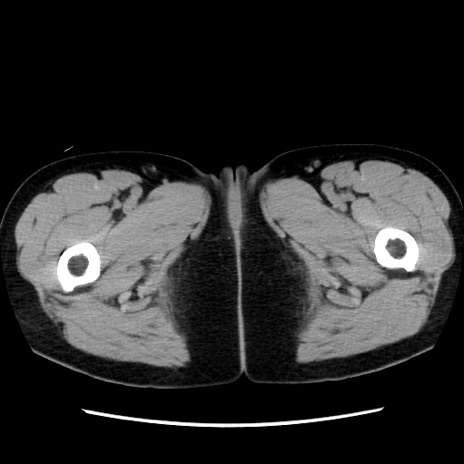

症例10(横断像)

【症例】 50歳代女性

【主訴】 腹痛

【現病歴】前日生レバーを食べた。今朝に排便あり。 昼前に突然発症の腹痛を生じ、当院救急外来を受診した。

【既往歴】 子宮筋腫にてで子宮全摘後

【身体所見】 意識清明、腹部:平坦、軟、下腹部やや左を中心に圧痛・反跳痛あり、筋性防御あり

【データ】WBC 7800、CRP 0.07